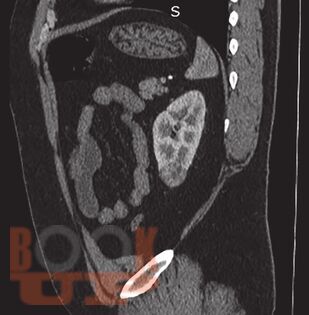

Трехтроакарная лапароскопическая резекция почки

В данном учебном пособии представлены сведения по анатомии и физиологии почек, эпидемиологии, этиологии, патогенезу, клинике, диагностике и современному хирургическому лапароскопическому лечению опухолей почек.